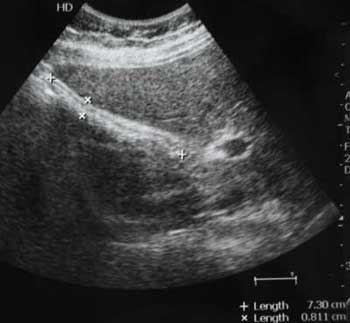

Молодой мужчина с болями в эпигастральной области.

Осматривался дважды натощак. Выявлены изменения желчного пузыря.

Печень, селезенка при УЗИ не изменены.

Прошу помочь с заключением.

Думаю,что это не просто пустой ж.пузырь,он содержит гиперэхогенное включение в середине,повторяющее форму ж.пузыря и дающее позадиакустическую тень.Возможна кальцифицированная аскарида

Нефункционирующий желчный пузырь содержит гиперэхогенное включение.

Первый ж.пузырь удален, клинический диагноз "сморщенный желчный пузырь, ЖКБ", гистология - фиброз стенок желчного пузыря.